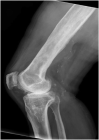

We present a case series comprising three patients with concomitant septic arthritis of the knee and osteomyelitis of the femur. Early advanced imaging rendered the accurate diagnosis of the condition and the appropriate surgical approach and technique used to treat the infection. Repeated extensive surgical debridement, irrigation and insertion of antibiotic-impregnated cement rod into the femur were required, in addition to long term antibiotics. The infection in all three cases was eradicated successfully. Following a period of physical rehabilitation, they had fairly preserved independent ambulatory function. We advocate a high index of suspicion of this condition with subsequent early advanced imaging for a timely diagnosis. In addition, we described our challenges in the fabrication process of the antibiotic-impregnated cement rod.